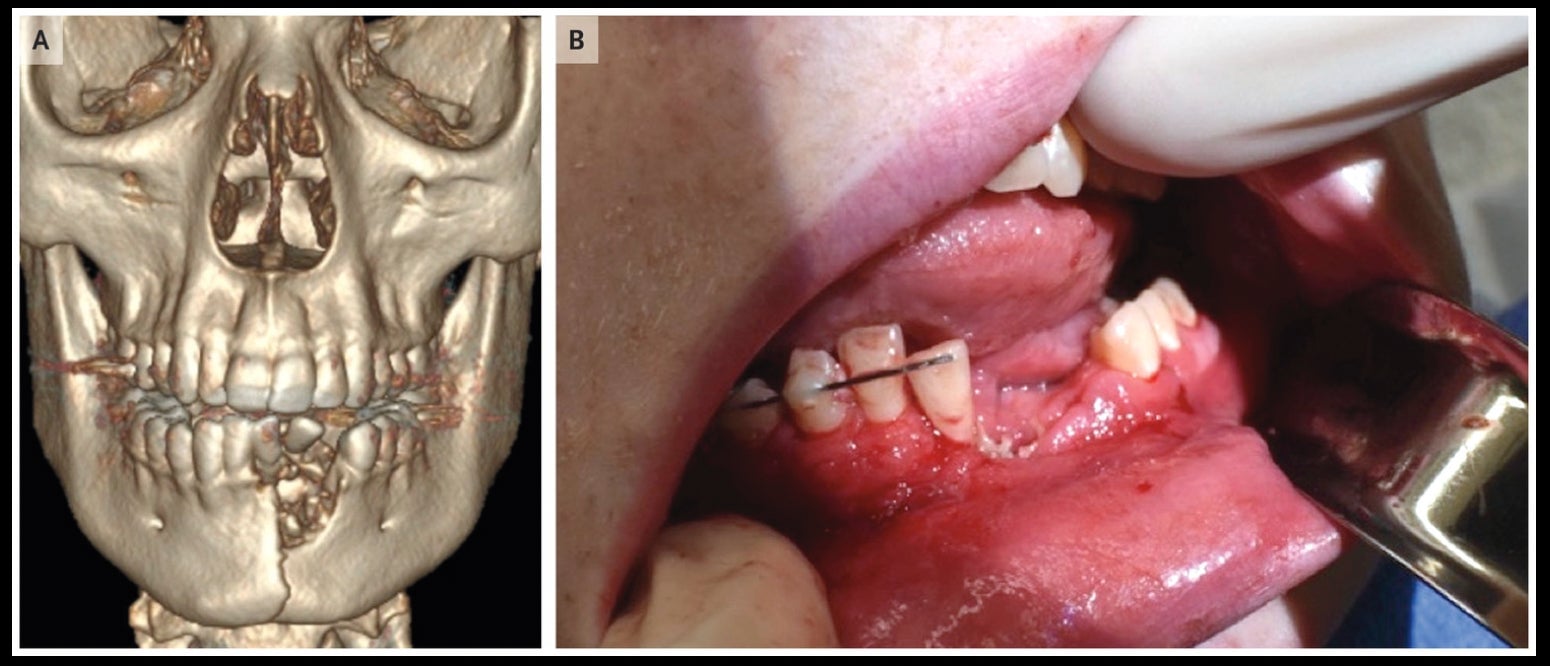

The doctors treating him observed a circular puncture to his chin and large gashes inside his mouth. A 3D scan of the teen’s head revealed the true extent of the damage.

“The vape blew up his lower jaw causing a major fracture and bone loss,” said Katie Russell, a pediatric trauma surgeon who treated the boy at the University of Utah Health Care and Primary Children’s Hospital in Salt Lake City. “He also lost multiple teeth, had a large cut in his mouth, and some lip burns.”

The hospital’s ear, neck, and throat surgeon added a plate to the teen’s lower mandible and wired the jaw shut. A dentist installed a small device (as shown in the photograph above) to secure the teen’s teeth while the jaw healed, explained Russell.